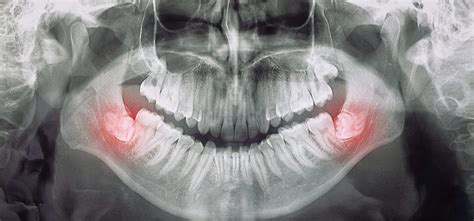

Protinių dantų skausmas nėra simptomas, kurį galima ignoruoti. Daugeliu atvejų jis reiškia, kad dantis dygsta netaisyklingai, uždegė ar jau pažeistas ėduonies. Laiku apsilankius odontologijos klinikoje, galima išvengti rimtesnių pasekmių ir užtikrinti sveiką šypseną ateityje.

Protinių dantų skausmas gali pasireikšti įvairiais simptomais ir būti sukeltas skirtingų priežasčių. Skausmą neretai lydi ir kiti nemalonūs pojūčiai ar požymiai. Tarp septyniolikos ir dvidešimt vienerių išdygstantys keturi protiniai dantys kai kuriems gali sukelti nemažai nemalonumų. Paprastai jų pasirodymas neturėtų sukelti didelio nepatogumo, tačiau dėl to, kad kiti 28 dantys jau būna užėmę savo pozicijas, kartais iškyla vietos stygiaus problema - šiems tretiesiems krūminiams dantims tiesiog nėra kur dėtis. Tokiais atvejais protinis dantis gali prasikalti per arti kito danties ar išdygti kampu. Dėl to galimas vidutinio sunkumo ar net stiprus skausmas.

Apsilankius odontologijos klinikoje, gydytojas gali parinkti tinkamiausią gydymo metodą: profesionalią burnos higieną ir uždegimo sumažinimą, dantenų „gaubto“ pašalinimą, kad nebekauptųsi bakterijos, antibiotikų skyrimą, jei yra infekcija, arba protinių dantų šalinimą - jei dantis nebeturi vietos, auga netaisyklingai ar kelia grėsmę kitiems dantims. Svarbu žinoti, kad protinio danties šalinimas yra viena dažniausių procedūrų odontologijoje ir ji atliekama saugiai bei efektyviai.

- Atlikti rentgeno nuotrauką, kad būtų galima įvertinti protinių dantų padėtį ir dygimo kryptį.